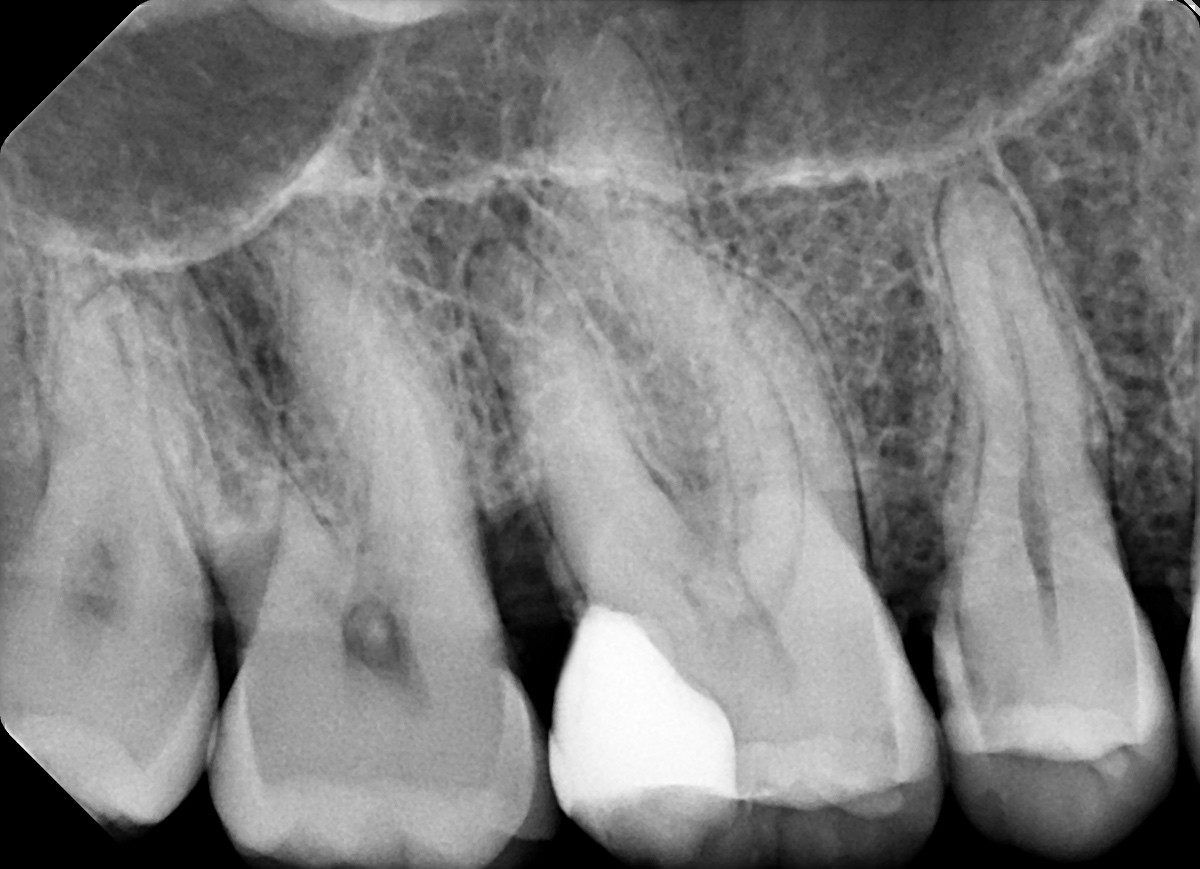

3. In the X ray bellow for which jaw periodontal bone loss is evident?